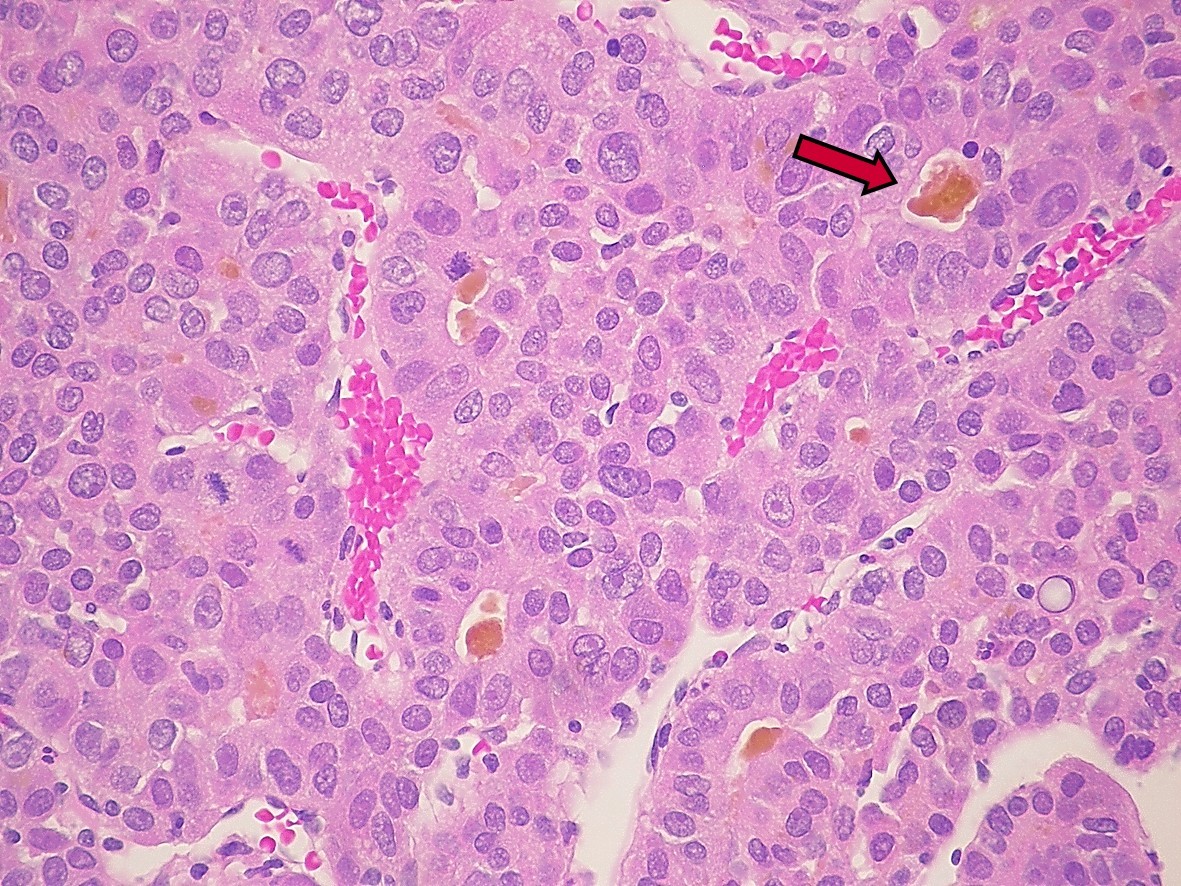

Patología Molecular

El diagnóstico sobre muestras de tejidos y líquidos corporales en plena era de la medicina del futuro, está basado en la integración de técnicas y conocimientos diferentes.

Hoy más que nunca es importante integrar una buena historia clínica con un correcto estudio de imagen y una buena morfología que además puede estar apoyada con proceso especiales complementarios relacionados con la Inmunología, Biología Molecular y Citogenética, generando así un estudio integral conocido como Patología Molecular.